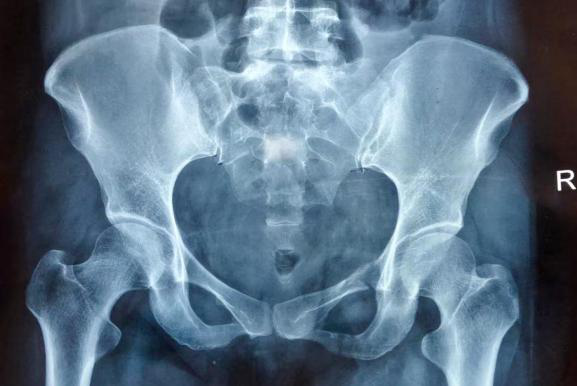

入院后完善了相关检查诊断:多发性骨盆骨折(Tile分型C 3型)、腰椎骨折、肺挫伤、创伤性胸腔积液。

术前X线片